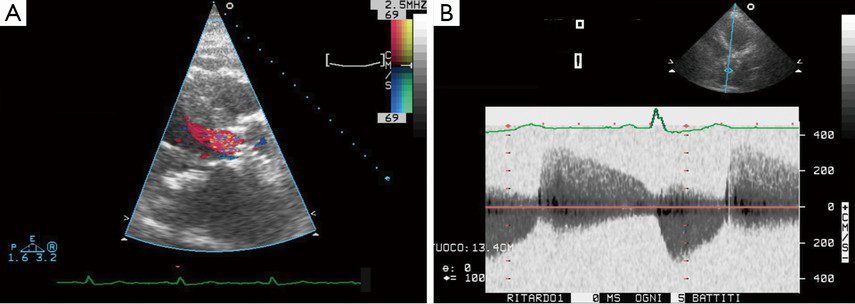

Predictive Factors Of Abnormal Dynamic Intraventricular ...

After valve replacement in severe aortic stenosis have been reported, although the incidence of DIG and clinical signs are still poorly understood. et al. Dynamic intraventricular gradient after aortic valve replacement ABBREVIATIONS DIG: dynamic intraventricular gradient AS: aortic stenosis ... Read Content